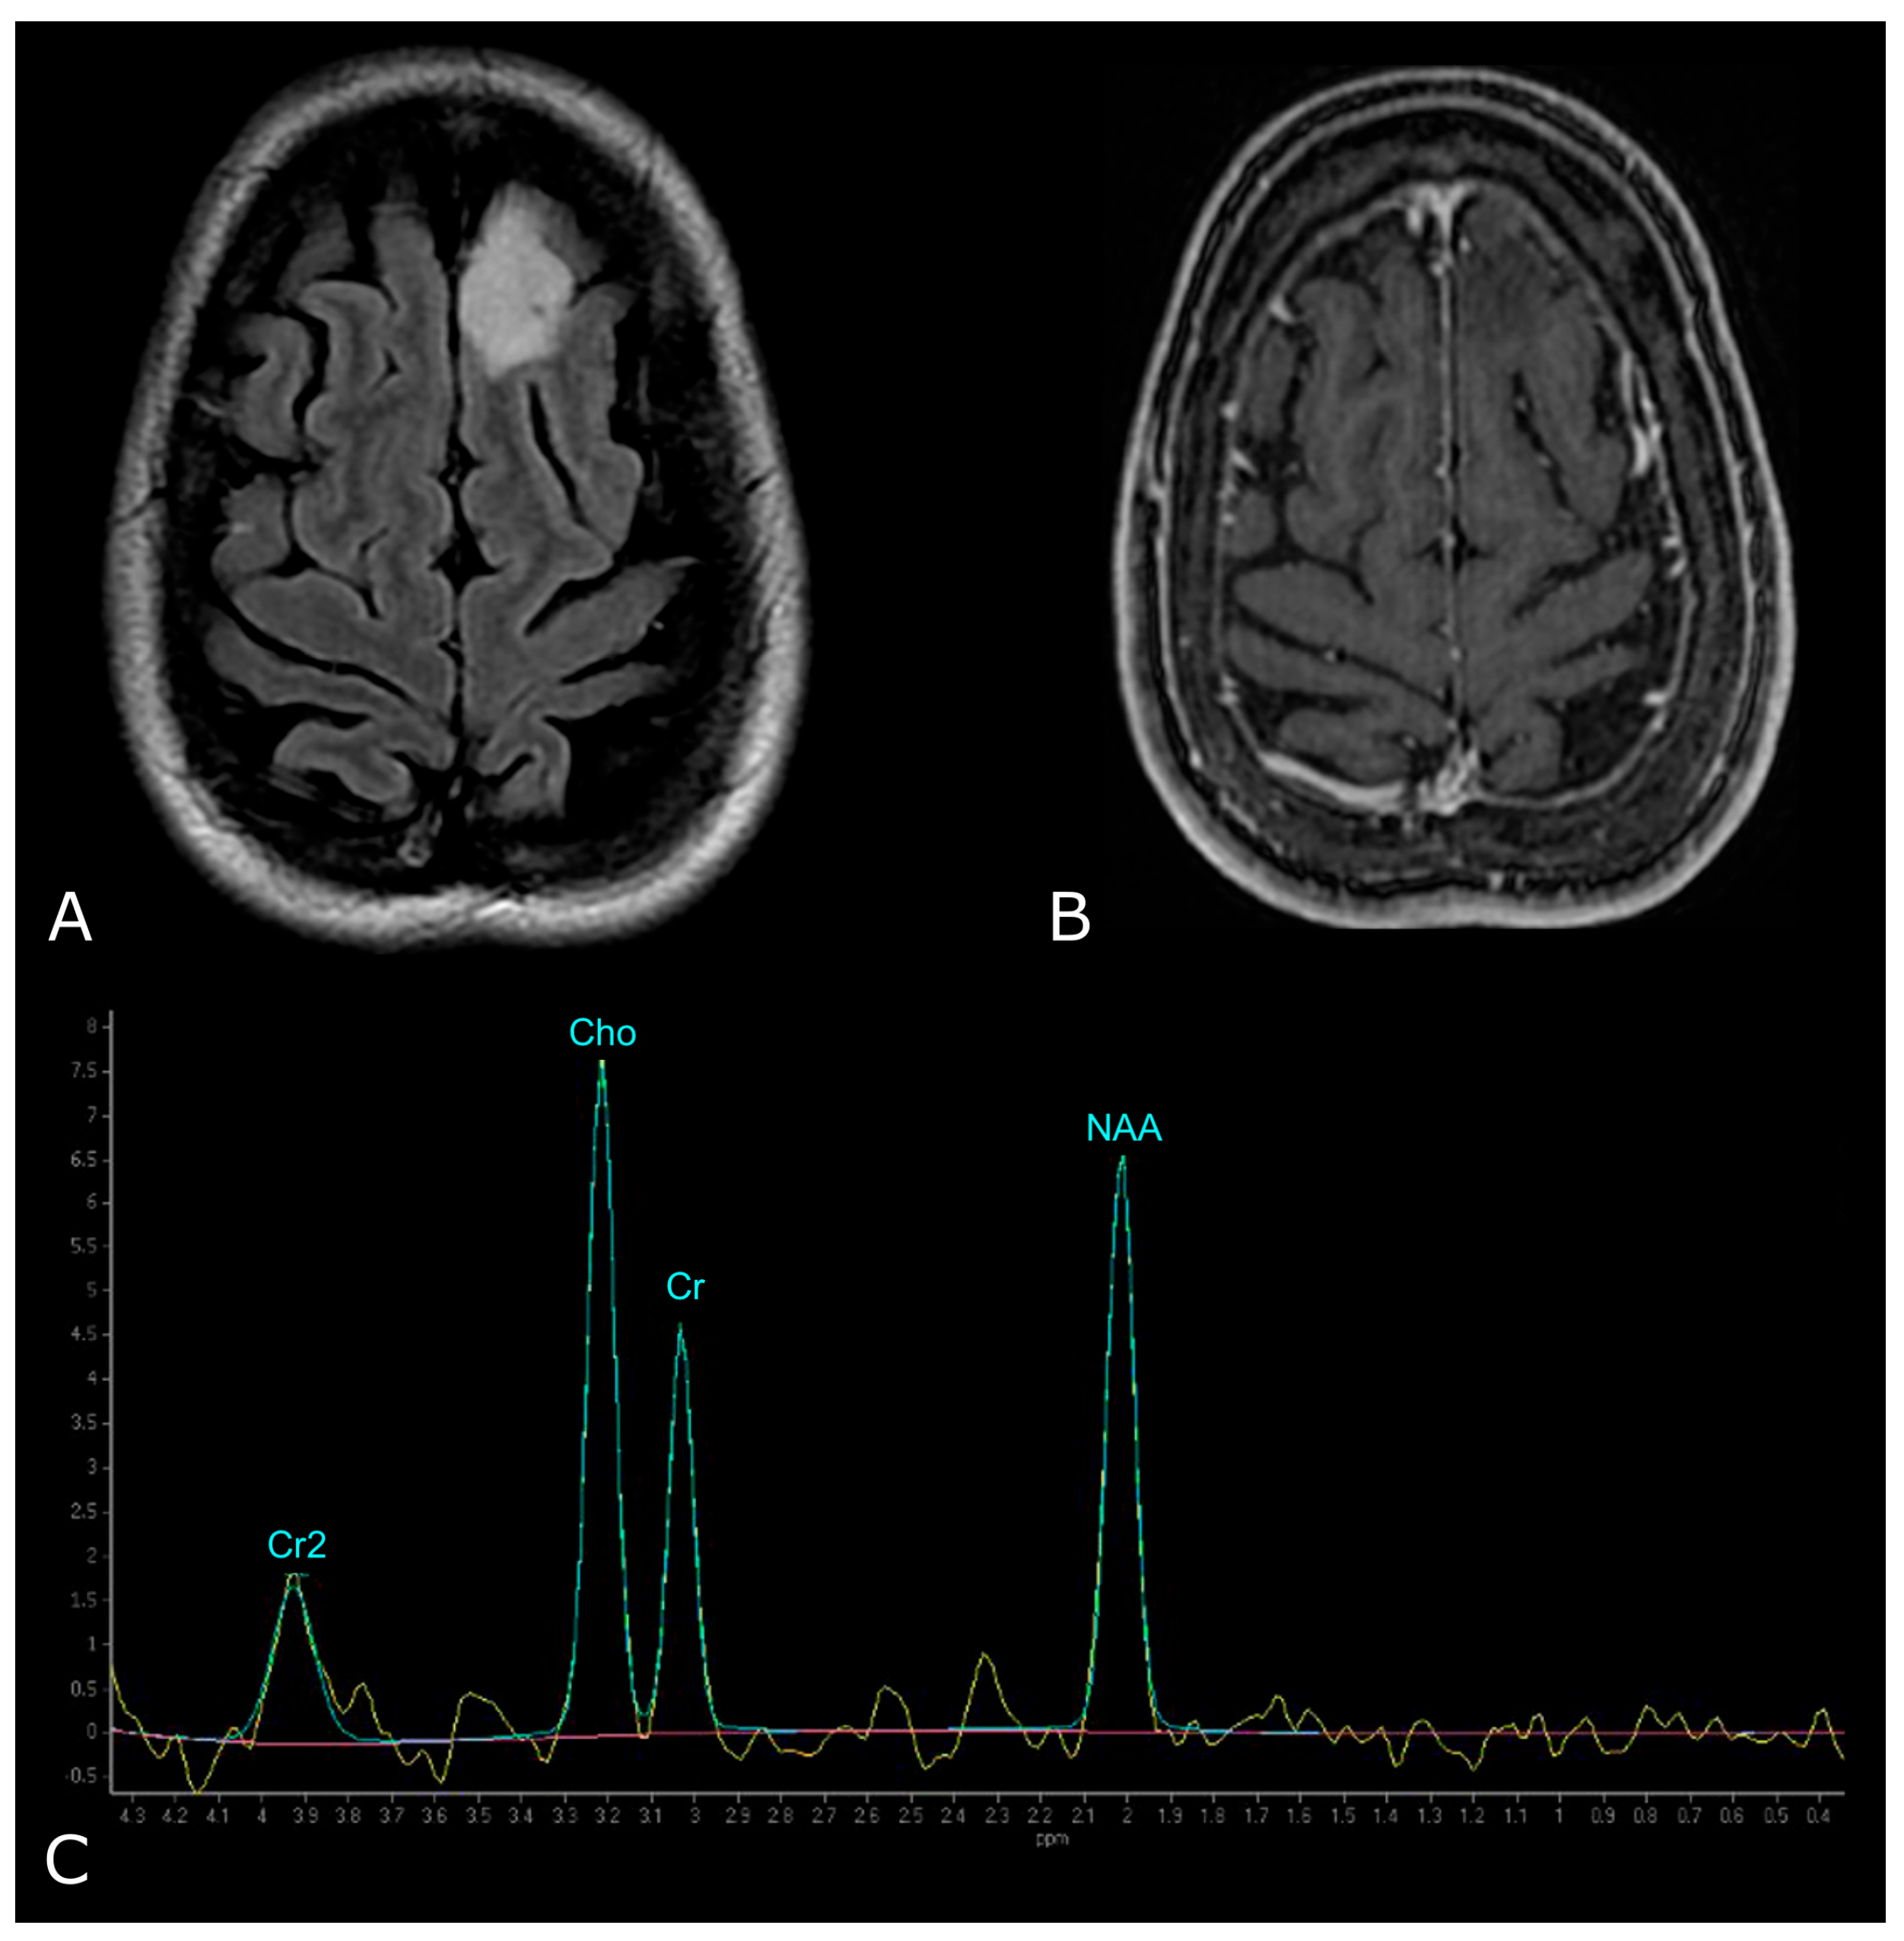

In proton MRS, the Time of Echo (TE) conditions the number of measurable neurometabolites. At short TE (e.g., TE = 35 ms or less) it is possible to detect the three main peaks normally observed in the brain—choline (Cho), creatine (Cr) and N-acetylaspartate (NAA)—and other compounds which may pathologically increase their concentration, such as myo-inositol (mI), lipids (Lip) and glutamate-glutamin (Glx). Using longer TE (TE = 144 or 280 ms), apart from Cho, Cr and NAA, it is possible to better detect the peaks of molecules with a longer T2, such as lactate (Lac) (Figure 8) [101]. The resonance peaks and biological significance of the major metabolites are listed in Table 3 [98,101,102,103]; unfortunately, there are no unequivocal cutoff metabolite signal ratios that clearly distinguish neoplastic from nonneoplastic conditions. Published MR spectroscopic results showed a sensitivity of 79% and a specificity of 77% for a choline/NAA ratio greater than 1 as an indicator of a neoplastic process [104]; the main ratios are listed in Table 4.

Figure 8.

Example of normal spectrum (SV TE 144ms). Normal MR spectrum demonstrating Cho, Cr and NAA peaks.

However, LGGs usually show either modest Cho elevation or NAA reduction, sometimes accompanied by increased mI and mI/Cr ratio (Figure 9). Moreover, LGGs typically lack Lac and Lip peaks, so that the appearance of Lac and Lip within the tumor is believed to suggest transformation to HGGs.

Figure 9.

MR Spectrum of LGG (SV TE 144ms). (A,B) Axial T2-FLAIR and post-contrast T1w of a left frontal low grade IDH-mut and 1p/19q-codeleted OD. (C) SV MRS demonstrates moderate Cho elevation and NAA reduction.

On the other hand, HGGs tend to have more dramatic MRS changes, including a marked increase in Cho and decrease in Cr, NAA, and mI. Thus, higher Cho/Cr and lower NAA/Cho ratios suggest HGGs as opposed to LGGs (Figure 10). To note, pilocytic astrocytomas are reported to have a low NAA/Cho ratio, despite their benign nature, and some authors have reported low Cho levels in HGGs, which may be due to the presence of necrosis [98,100].

Figure 10.

MR Spectrum of HGG (SV TE 144ms). (A,B) Axial T2-FLAIR and post-contrast T1w of a right parietal HGG, with necrotic areas; (C) SV MRS demonstrates a prominent increase in Cho and a decrease in NAA, with high Cho/Cr and low NAA/Cho ratios. Double negative peak of lactates is also present, consistent with the presence of necrosis.